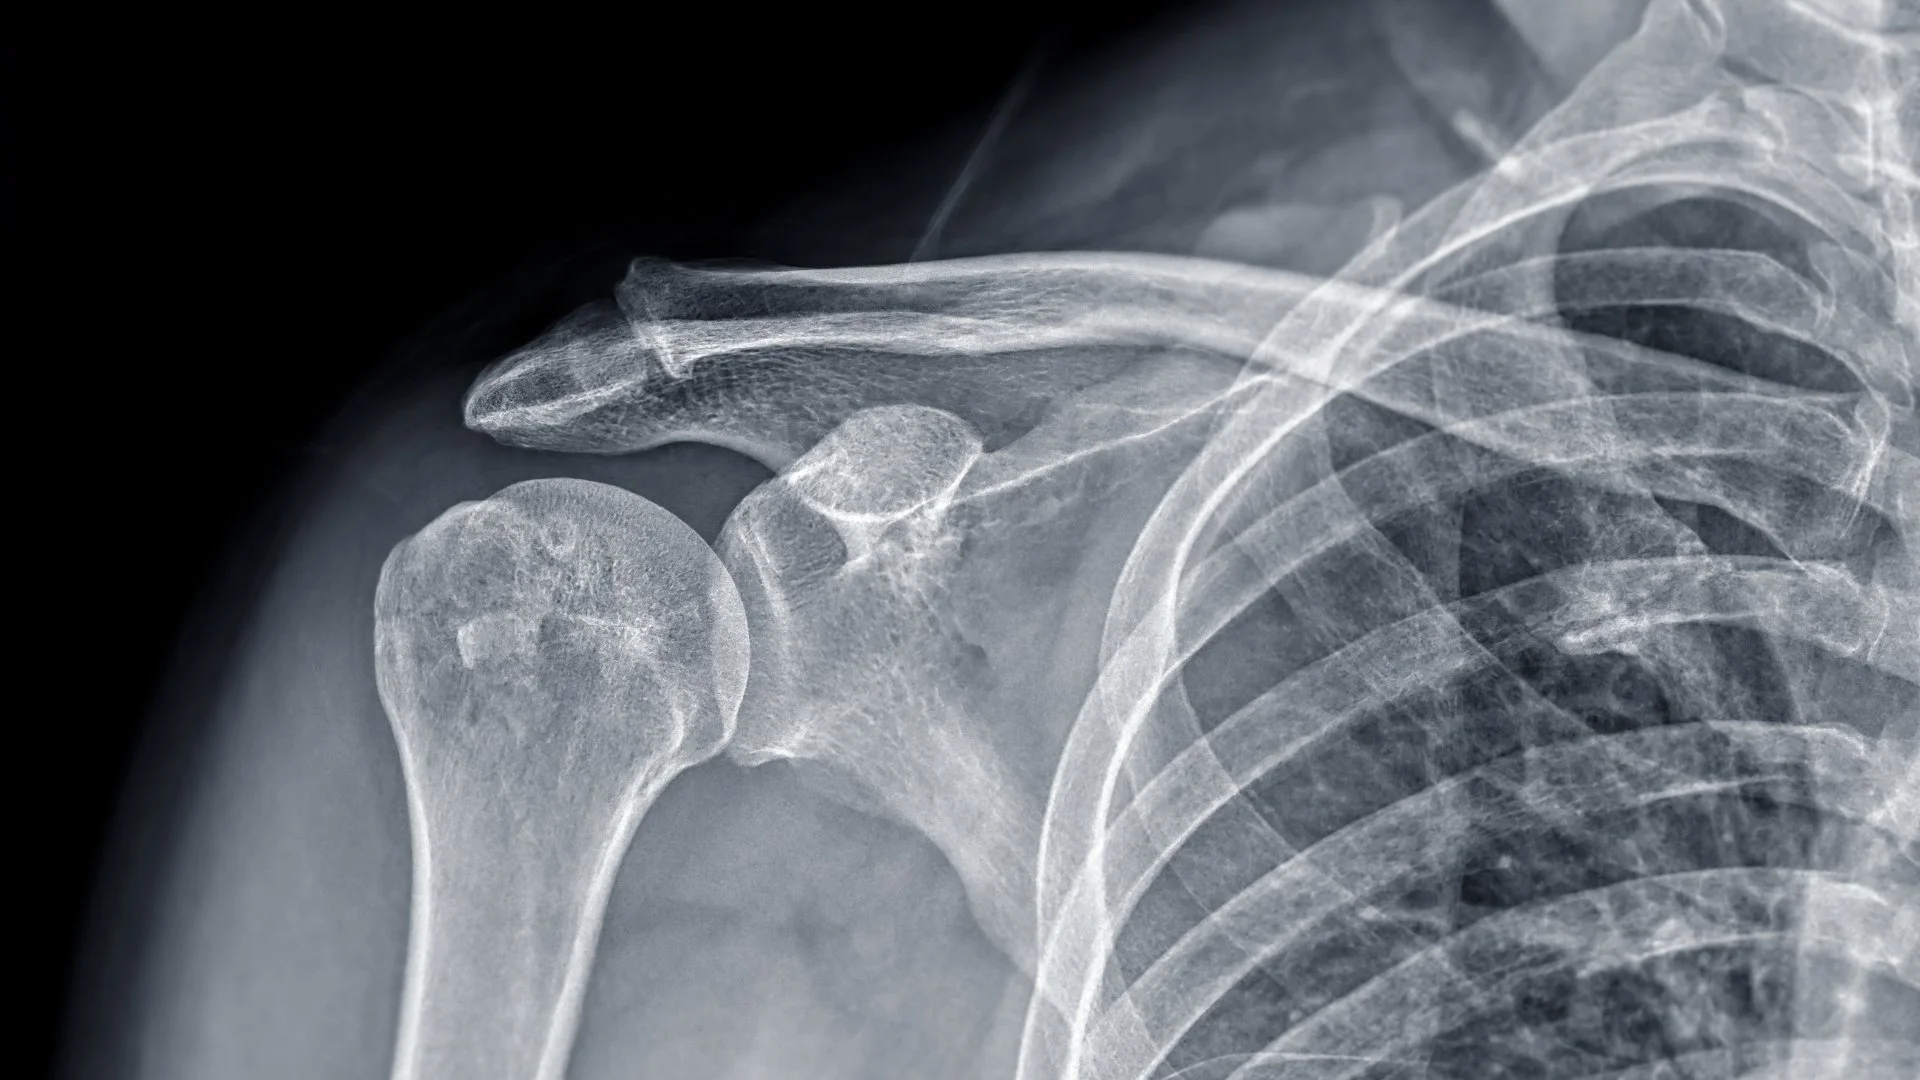

Son un estudio de diagnóstico por imagen que permite visualizar el hueso de la escápula, también conocido como omóplato, el cual se encuentra en la parte posterior del hombro y forma parte fundamental de la articulación del hombro.

• Los rayos X de escápula permiten identificar fracturas, fisuras, luxaciones o cambios en la estructura del hueso. También ayudan al médico a evaluar si existe alguna alteración en la articulación del hombro relacionada con el omóplato.